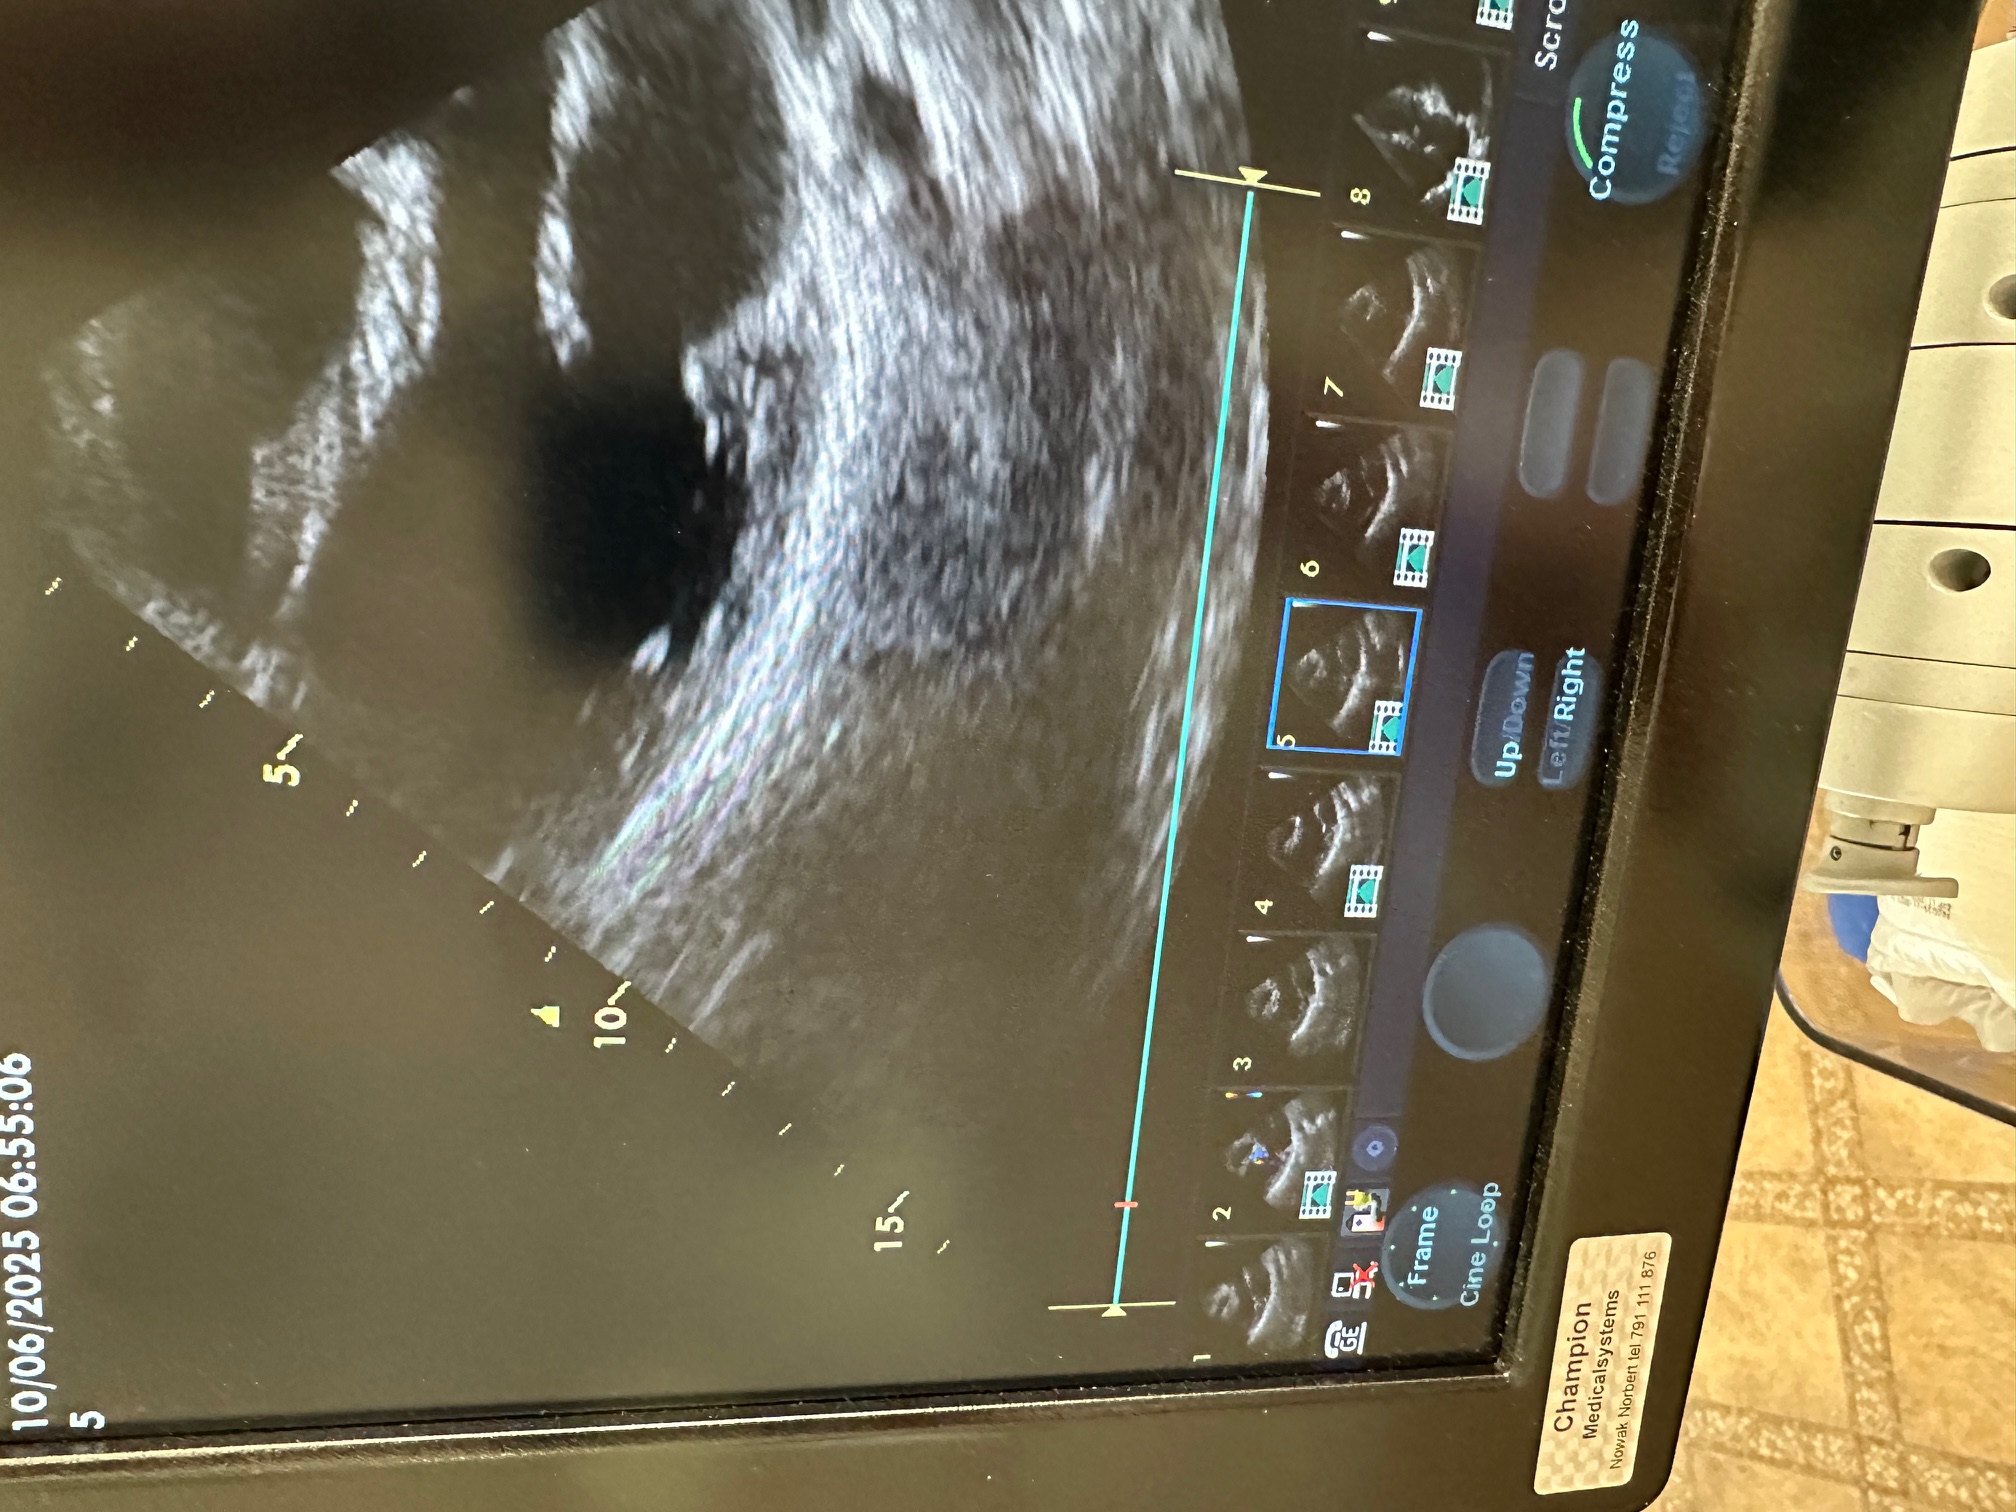

oferuję echokardiograf Vivid S6 z 2014r z głowicą M4S Rs z 2023r.

Aparat sprawny z aktualnym paszportem.

Głowica praktycznie bez śladów użytkowania - wykonane maksymalnie 100 badań.

oferuję echokardiograf Vivid S6 z 2014r z głowicą M4S Rs z 2023r.

Aparat sprawny z aktualnym paszportem.

Głowica praktycznie bez śladów użytkowania - wykonane maksymalnie 100 badań.